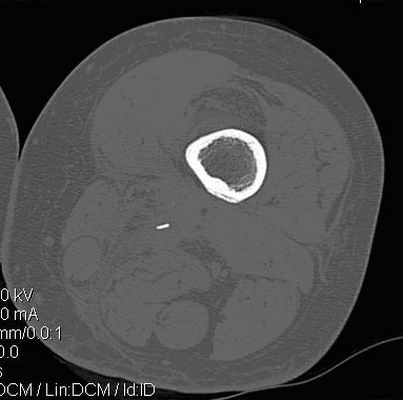

Компьютерная томография имеет более высокую инфрмативность и в определении стадии остеомиелита, так как дает возможность получения изображения на интересуемом уровне в аксиальной проекции и проведения не только качественной, но и количественной оценки. С помощью компьютерной томографии у половины пациентов (20 человек - 50%) удалось выявить особенности костной деструкции, визуализировать секвестры, воспалительные кисты в мягких тканях, параоссальные флегмоны, абсцессы и другие изменения, которые не определялись рентгенологически. Кроме того, проведенные томографические исследования позволяли четко определиться с анатомическим расположением патологического очага, его взаимосвязью с окружающими структурами (рис. 4, 5). Компьютерная томография повлияла на принятие тактического решения у 11 пациентов (27,5%). С помощью КТ-фистулографии у 19 (47,5%) пациентов дополнительно определялось распространение контрастного препарата по свищевым ходам как в мягких тканях, так и в кости. Во всех случаях выявленные поражения на КТ-фистулографии подтвердились операционными данными.

Рис. 4. Компьютерная томограмма левого бедра пациентки П., 45 лет с хроническим посттравматическим остеомиелитом. Выявлен мелкий секвестр в мягких тканях не визуализирующийся на рентгенограммах